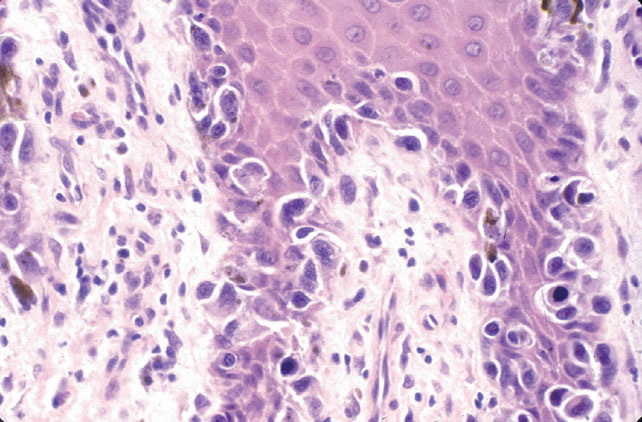

Acral melanoma =ميلانوم النهايات